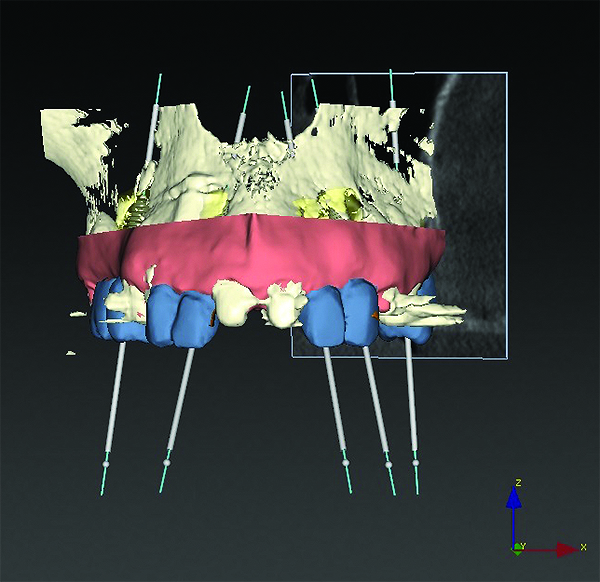

3D radiographic scans obtained using the single scan protocol can be combined with digital mock-ups performed on intraoral optical scans or scans of casts,20 using the existing natural teeth as fiduciary markers. Different masks for bone, teeth, gingiva, and implants can be designated and processed (Figure 13 and Figure 14). This technology allows for greater accuracy, since implant position will be determined based on natural teeth (fiduciary markers) that are likely to be more stable and accurate than fiduciary markers placed on a radiographic guide.

(13) An optical scan of patient’s teeth and diagnostic wax-up was combined with CBCT to facilitate treatment planning of implant placement. Note that there is a need for sinus augmentation to accommodate a dental implant on the right image (blue: tooth contours determined from wax-up/optical impression, red: soft tissue outline).

Figure 13

(14) An optical scan of patient’s teeth and diagnostic wax-up was combined with CBCT to facilitate treatment planning of implant placement. Note that there is a need for sinus augmentation to accommodate a dental implant on the right image (blue: tooth contours determined from wax-up/optical impression, red: soft tissue outline).

Figure 14